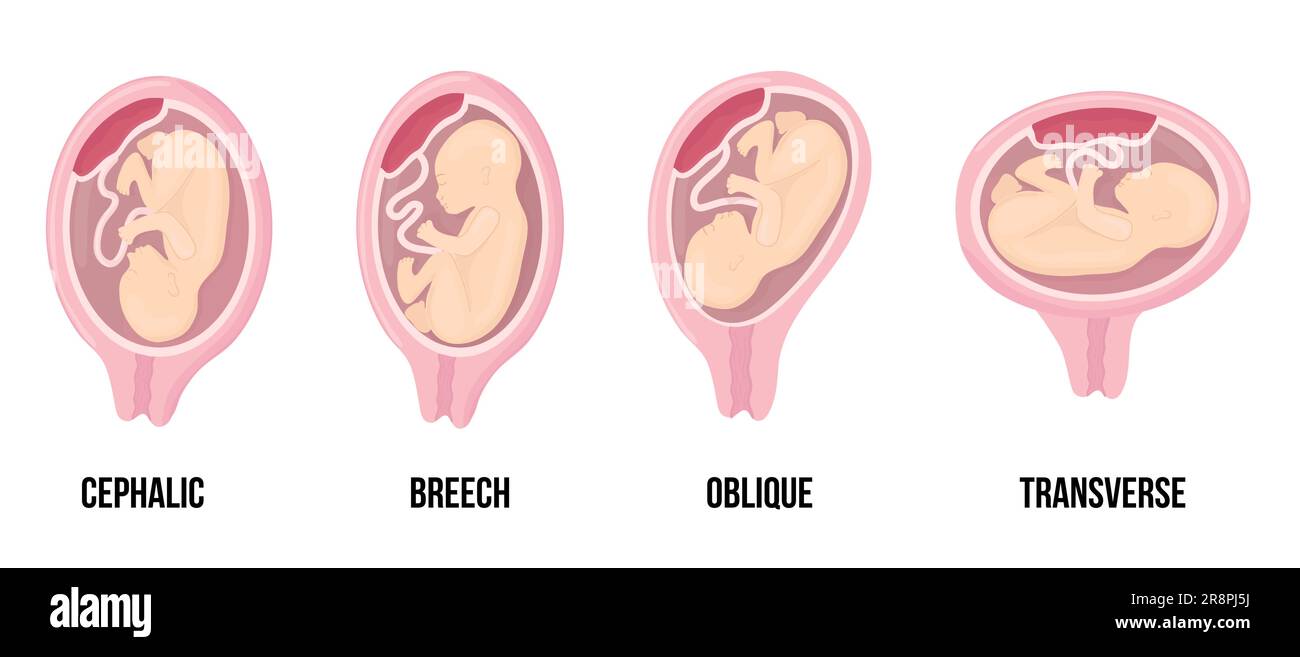

Different wrong baby positions in uterus during pregnancy. Cephalic, Breech, transverse, Oblique lies. Colored medical vector illustration. Fetus with Stock Vectorhttps://www.alamy.com/image-license-details/?v=1https://www.alamy.com/different-wrong-baby-positions-in-uterus-during-pregnancy-cephalic-breech-transverse-oblique-lies-colored-medical-vector-illustration-fetus-with-image556146238.html

Different wrong baby positions in uterus during pregnancy. Cephalic, Breech, transverse, Oblique lies. Colored medical vector illustration. Fetus with Stock Vectorhttps://www.alamy.com/image-license-details/?v=1https://www.alamy.com/different-wrong-baby-positions-in-uterus-during-pregnancy-cephalic-breech-transverse-oblique-lies-colored-medical-vector-illustration-fetus-with-image556146238.htmlRF2R8PJ5J–Different wrong baby positions in uterus during pregnancy. Cephalic, Breech, transverse, Oblique lies. Colored medical vector illustration. Fetus with